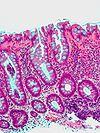

Tubular Adenoma (Villous, Tubulovillous) Colorectal Tubular glands with elongated nuclei (at least low-grade atypia) Yes

Tubular adenoma 2 high mag.jpg